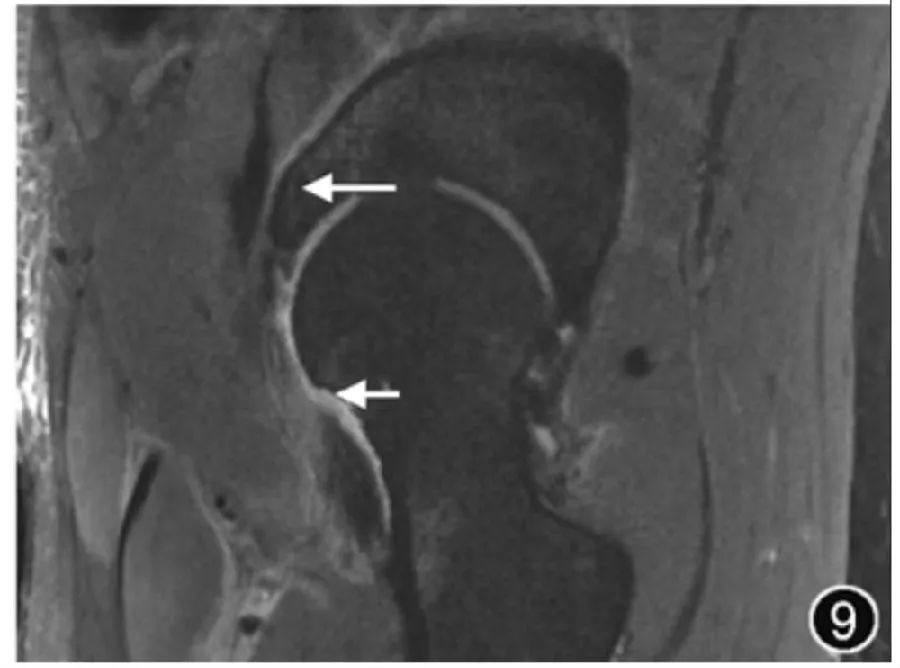

8.Послеоперационная оценка тазобедренного сустава: артроскопия тазобедренного сустава, хирургия губы, остеохондропластика (рис. 9) и эндопротезирование тазобедренного сустава широко используются у пациентов с травмами тазобедренного сустава. Остаточные или рецидивирующие разрывы верхней губы можно диагностировать, когда после восстановления губы наблюдаются значительные сигналы жидкости в суставную губу и/или соединение хрящевой губы. Во время последующего обследования после операции по замене тазобедренного сустава МРТ является наиболее точным методом визуализации для оценки перипротезного остеолиза и синовита. Она также позволяет оценить соответствующие сухожилия и нервно-сосудистые структуры в области хирургического вмешательства. Рентгенологическая оценка после замены тазобедренного сустава должна учитывать распространенные послеоперационные осложнения, которые в основном включают перипротезный остеолиз, расшатывание и смещение протеза, послеоперационную инфекцию, гемартроз, синовит, скрытые переломы, а также оссификацию участка, а также дегенерацию и разрывы окружающих мышц. сухожилия. При других операциях на бедре, таких как внутренняя фиксация переломов шейки бедренной кости, следует обратить внимание на наличие послеоперационных осложнений, таких как аваскулярный некроз головки бедренной кост

Рисунок 9. МРТ-изображение после операции по поводу импинджмента бедра. Корональная Т2-ВИ показывает ход винта вертлужной впадины (длинный ↑) и локальный дефект кости в головке и шейке бедренной кости (короткий ↑), а также отек окружающих мягких тканей.